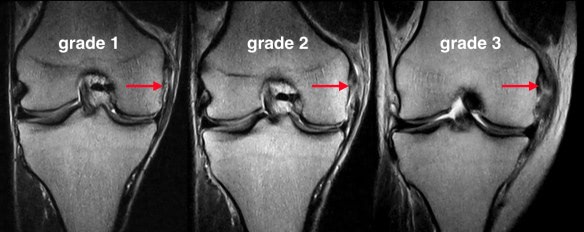

Answer: C) Grade 2

Explanation: Grade 2 sprain is a partial tear. On MRI a high signal with partial ligament disruption is seen

A) is incorrect as this is not a valid grade.

B) is incorrect because grade 1 is mild stretch with intact fibres.

D) is incorrect because grade 3 is a complete rupture with no continuity.

E) is incorrect because grade 4 is not part of standard classification.